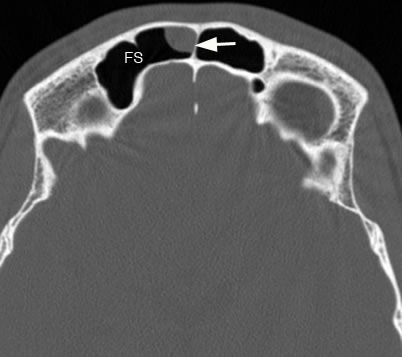

Axial image of the frontal sinuses (FS) with arrow pointing to a mucus retention cyst along the non-dependant right frontal sinus air cell.